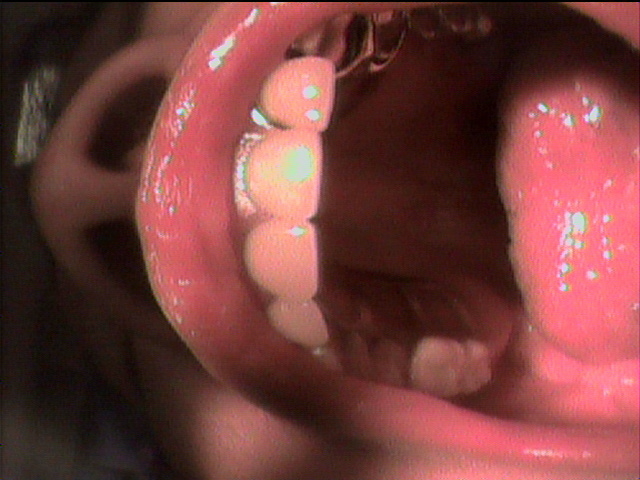

上の入れ歯がこわれてしまって、来院されました。のこっている上の前歯の6本分がつながったブリッジは歯ぐきが根元ではれていてぐらぐら状態。全く噛む場所がありません。

診断すると、残っている前歯4本は歯の中がほとんどくさってしまっていました。

残念ながら前歯はすべて抜かなくてはならず、上の歯は総入れ歯としてまず治療用入れ歯を事前に準備することから開始しました。同時に歯ぐきの腫れの消炎処置をしました。

前歯のつながった歯を切り離し、同時に歯を抜き、その日にすぐに仮の入れ歯を装着することとしました。

顎の粘膜の調整をしながら経過し、上の入れ歯との噛み合わせを調整していきます。

顎の状態が良好になってきました

約2ヶ月後最終入れ歯を入れた状態です。

初診から最終調整まで、前歯がなくなってしまう見栄えが悪い事は一日もなく治療を進行することができました。

現在 右も左もしっかりと噛む事が出来ます。